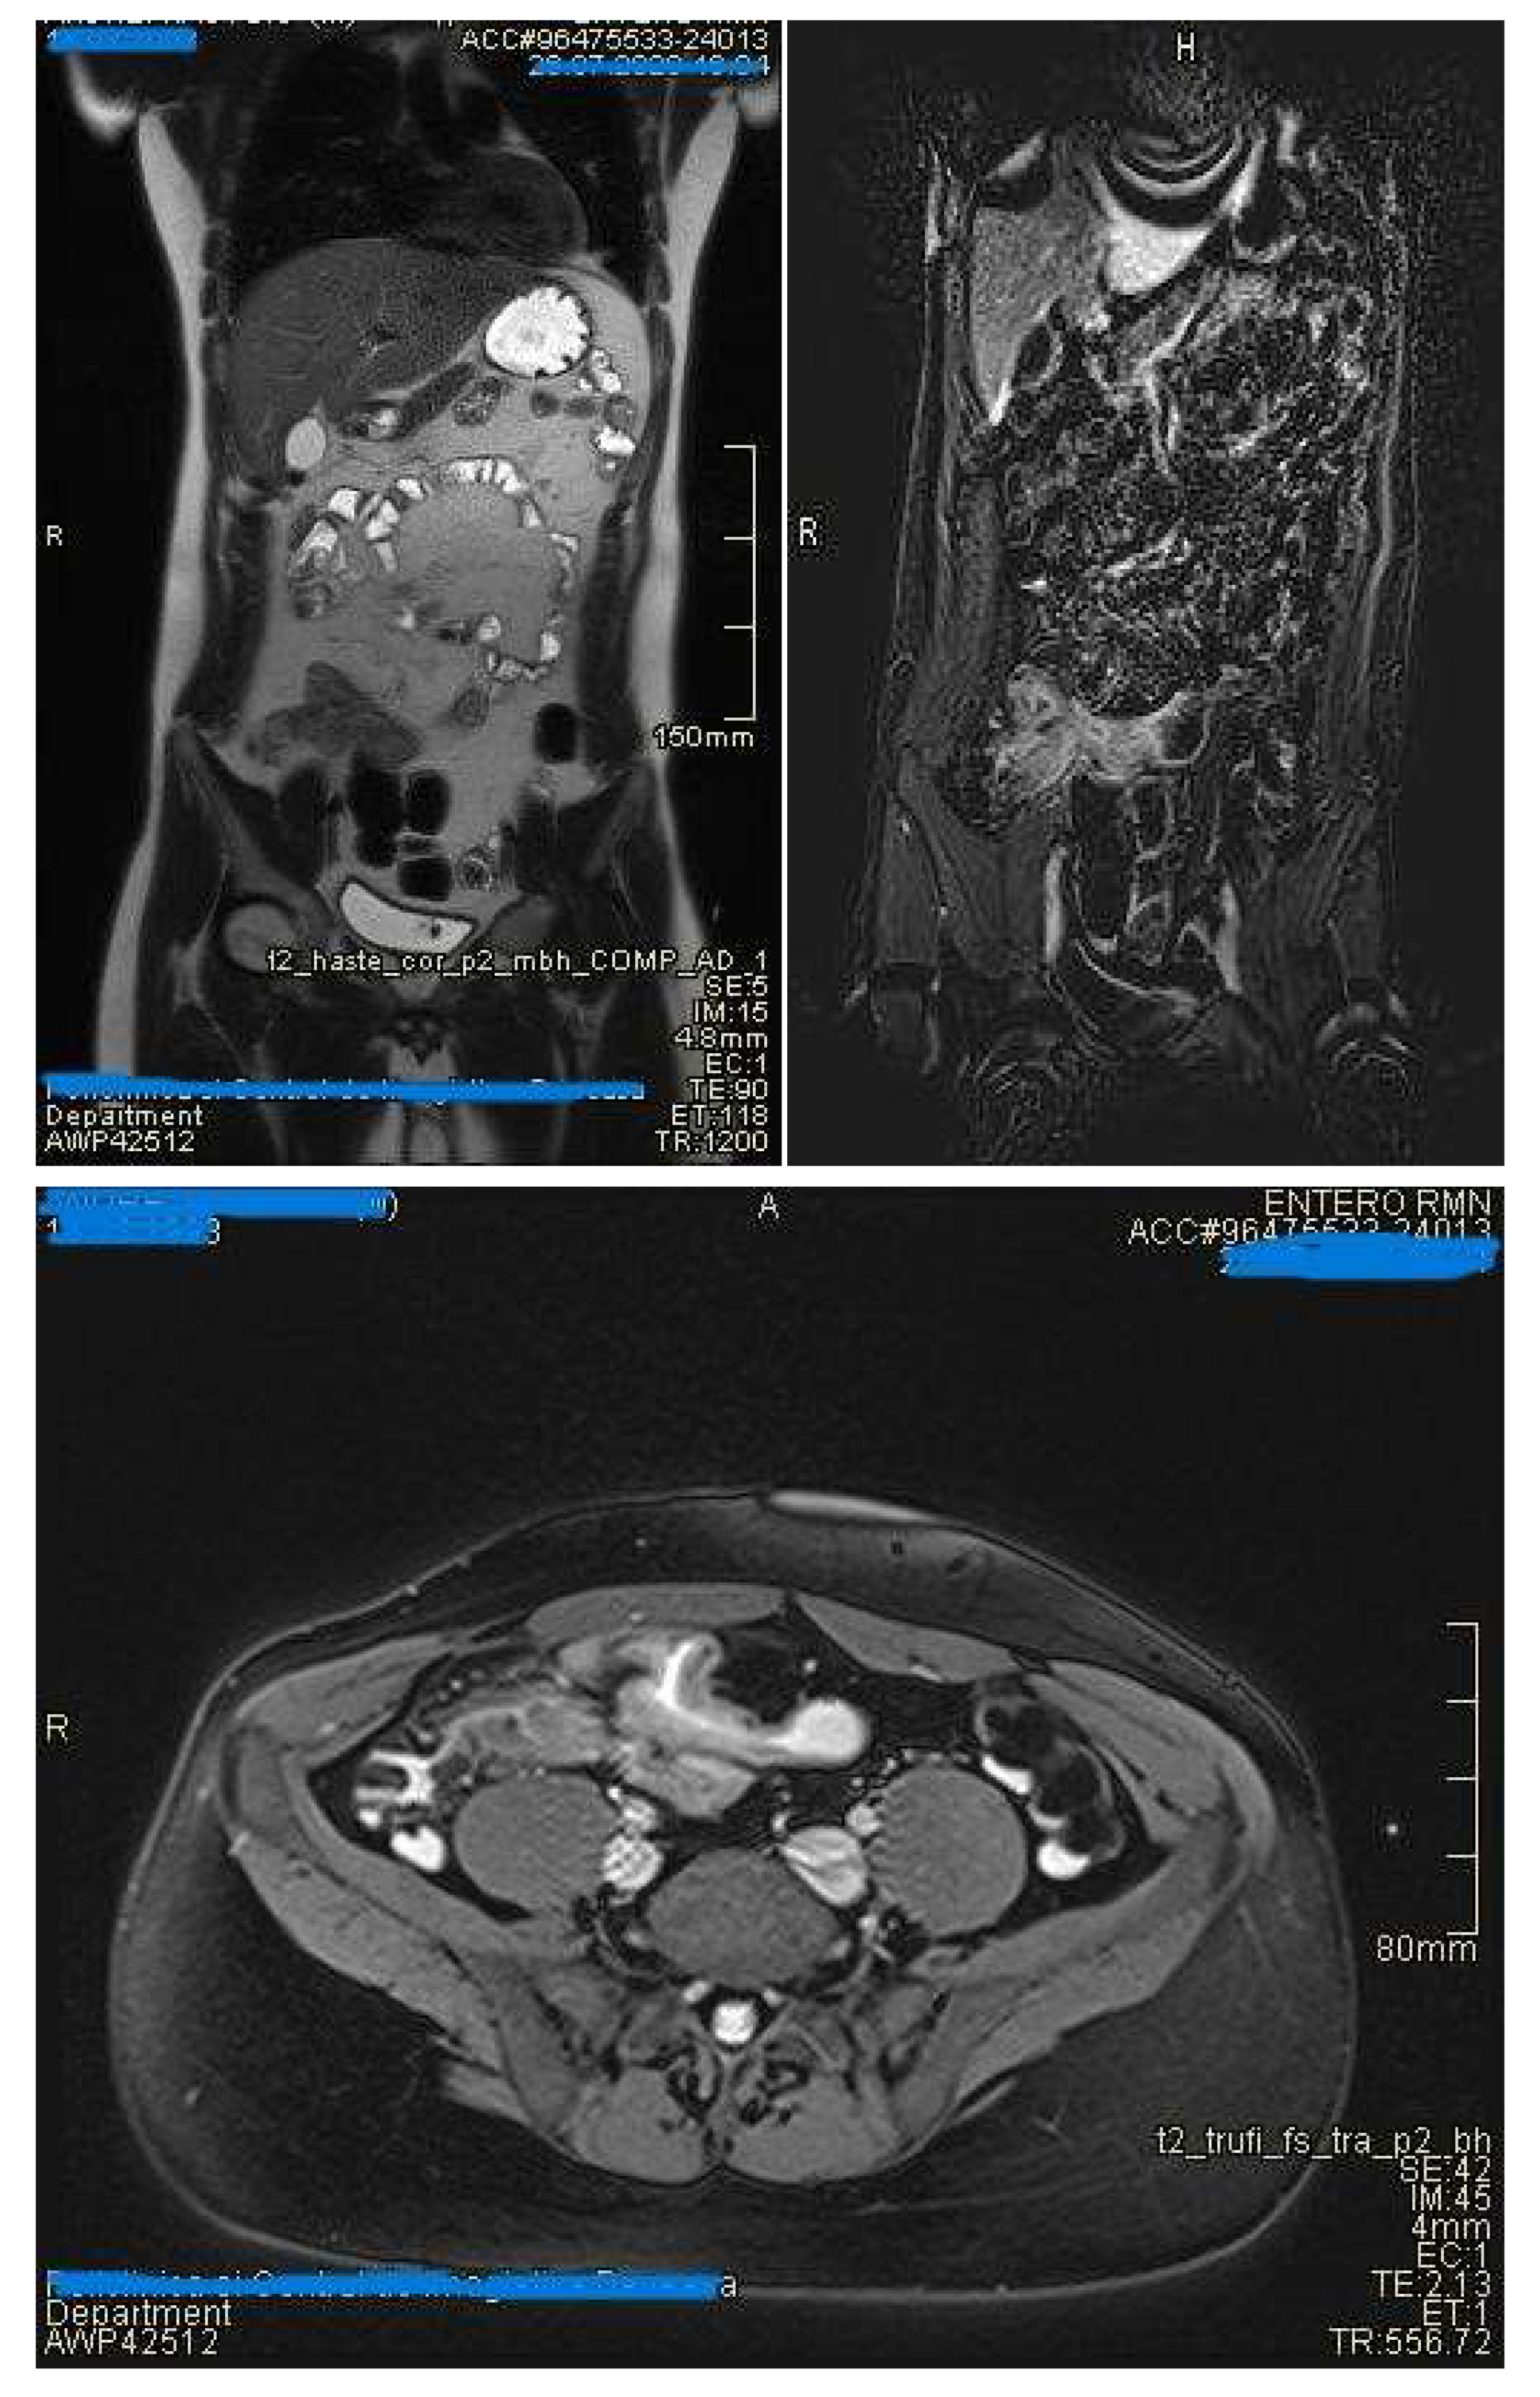

- Mural thickening :

- Is mild (<5 mm), moderate (<9mm) and severe (> 10 mm)

- Commonly occurs in active areas of inflammation (Figure 1).

- Mural hyperenhancement

- Asymmetric distribution in CD or ontinuous and concentric distribution in extensive ulcerative colitis[44]

- Stratified uptake: “double layer” (submucosa is thickened by edema and inflammation) or “trilaminar layer” (when serosa is also involved) [8]

- Homogeneous, hypovascular uptake in (chronic) fibrosis

- Correlates with clinical and biological activity scores [44]

- Evaluated on post-gadolinium T1 fat-sat sequences, in dynamics [50]

- Intramural edema

- Is detected as T2 hyperintense signal

- Restricted diffusion

- DWI hypersignal + low ADC in acute inflammation

- May be inflammatory (with edema and entrapment) or fibrotic (without inflammatory signs)(Figure 7)